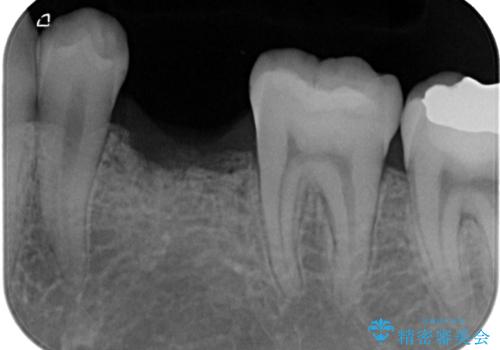

- 乳歯を抜歯したところにインプラントをしたいと来院された患者様です。

永久歯の先天欠如による乳歯の晩期残存があり、その乳歯が虫歯になってしまい保存不可能になり、他院で抜歯をし義歯を使用していた状態です。

義歯では嚙みづらいため、インプラントによる補綴をしていくこととしました。

なお、反対側も永久歯先天欠如による、乳歯の残存がありますが、特に齲蝕も認められないため処置をせず、できるだけ保存していくこととしました。